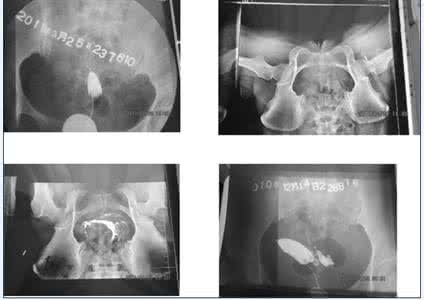

输卵管造影经X线的子宫输卵管造影是通过导管向宫腔及输卵管注入造影剂,利用X线诊断仪行X线透视及摄片,根据造影剂在输卵管及盆腔内的显影情况来了解输卵管是否通畅、阻塞部位及宫腔形态的一种检查方法。